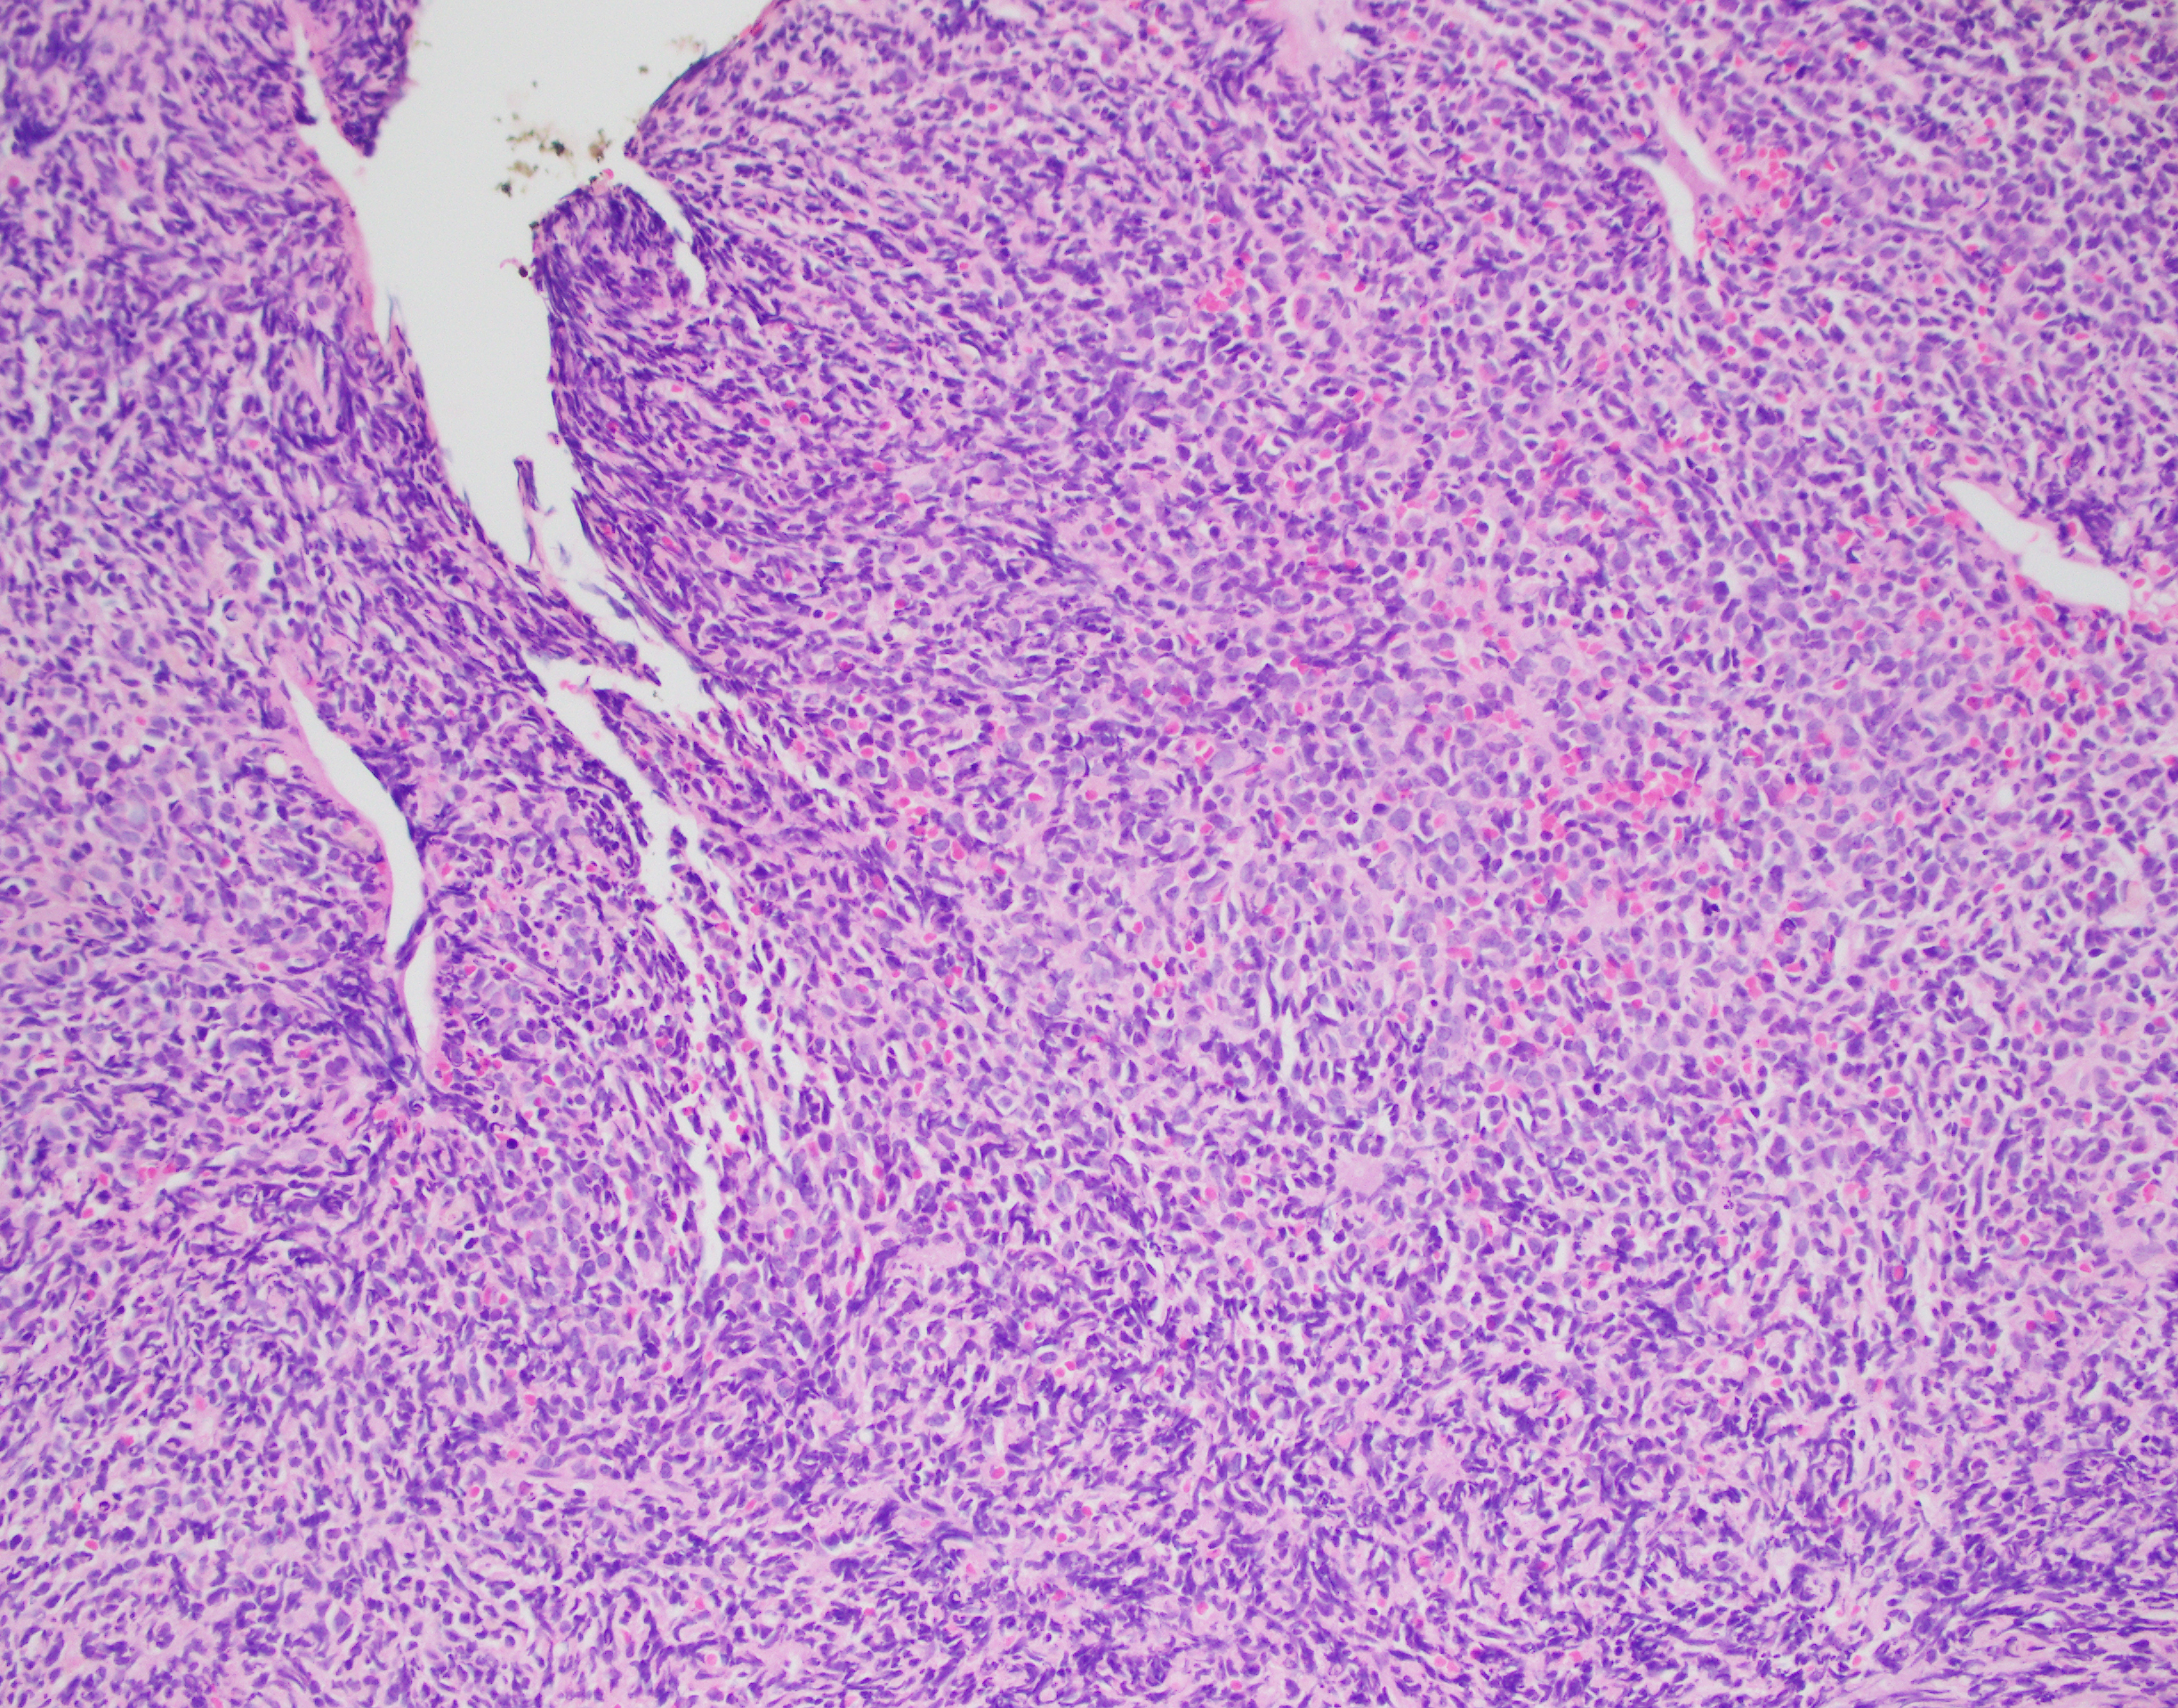

Essentially, this patient was found to have Li-Fraumeni after the second manifestation of an acute sarcoma—the first being osteosarcoma in her teenage years and the second breast cancer in her 30s. Both cancer diagnoses were treated accordingly, and this patient was going through routine work-up for anemia before being referred to the Mayo Clinic. By the time the patient reached there, the clinical investigation included a battery of testing for causes of anemia—all within normal limits—so a bone marrow examination was performed which revealed a significant, though not acute (<20% blasts), myelodysplastic process. A follow-up in-house bone marrow collection revealed hypercellular marrow, now in acute myeloid proliferation, with abnormal myeloid cell maturation and very complex cytogenetics. She had a very complex karyotype and several detectable mutations which were consistent with the WHO’s classification and description of therapy-related myeloid neoplasm as a sequale to the treatments she received for her prior cancers. In the setting of a patient with LFS, it is almost impossible to avoid malignancy. The following slides are a (very abridged) summary taken from my presentation of this patient’s case:

There are two main reasons why all of this is important enough to discuss in a case conference. First, as clinicians from the bench to the bedside we should all strive to talk through the toughest diagnoses and share with each other what best practices, lessons, and goals we can reach together. In the setting of Li-Fraumeni Syndrome it becomes critical to evaluate new onset (especially myeloid) neoplasms. TP53 mutations are associated with the lowest survival rates in acute myeloid leukemia, which has its own diagnostic and prognostic classifications set forth by the World Health Organization. Furthermore, understanding appropriate patient history, clinical information, and what appropriate lab investigation means is crucial. It not only keeps the needs and interests of the patient first, but also translates to the proper utilization of resources for the best results in the best timelines. Potential future implications of concurrent ongoing work in hematopathology and molecular genetics may yield therapeutic and diagnostic benefits we are not yet aware of—we must constantly include updates as we practice.

- Acute Myeloid Leukemia and Myeloid Sarcoma